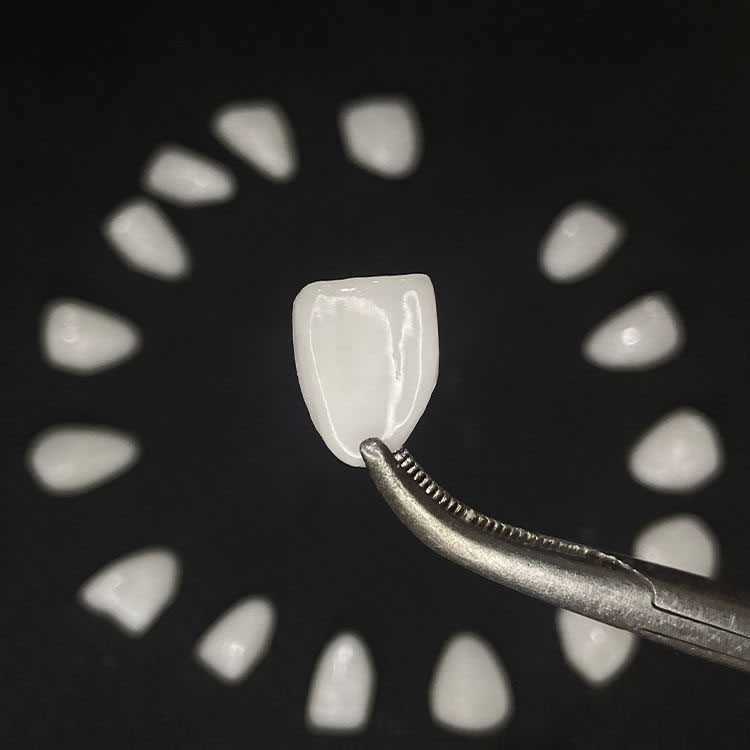

Most people talk about E.max veneers as if the brand name settles the argument, but that is lazy thinking, because a full E.max veneer is a monolithic lithium-disilicate restoration while a layered E.max veneer adds porcelain build-up to a lithium disilicate base to chase more depth, vitality, incisal effects, and texture. So the real difference is not the logo. It is the amount of variability you are willing to buy into.

A full E.max veneer is monolithic lithium disilicate, usually finished with stain, glaze, gloss control, and surface texture rather than with an added veneering porcelain layer, which is why labs sell it as the more repeatable route for multi-unit smile cases where fit, value control, and cross-unit consistency matter more than showing off a ceramist’s incisal magic. That is also why I tend to trust it more when the doctor wants canine-to-canine discipline, not a single hero central incisor.

A layered E.max veneer starts with a lithium disilicate core and then adds porcelain layering to build depth, translucency gradients, halo effects, and surface texture, which is exactly why it can look outstanding in high-end anterior work and exactly why it becomes less forgiving when the prep space is inconsistent, the stump shade is sloppy, or the photos are weak. Beautiful? Absolutely. Automatic? Not even close.

The real difference is that full E.max veneers are monolithic lithium-disilicate restorations made as one ceramic body, while layered E.max veneers combine lithium disilicate with added porcelain to create more incisal effects, texture, and optical depth, which raises the esthetic ceiling but also increases technique sensitivity and workflow variability. After that, everything else is just detail.